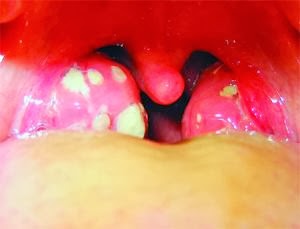

হয় না। অনেক সময় গলার

বাইরের দিকে দুই পাশে বরই বিচির মতো দুটি দানা ফুলে উঠতেও দেখা যায়, অনেকে এগুলোকে টনসিল মনে করলেও এরা কিন্তু

টনসিল নয়। রোগী বড় করে মুখ হাঁ করলে ভেতরের দিকে যে দুটি বড় দানার

মতো দেখা যায়, তা-ই হলো টনসিলাইটিসে

আক্রান্ত টনসিল।